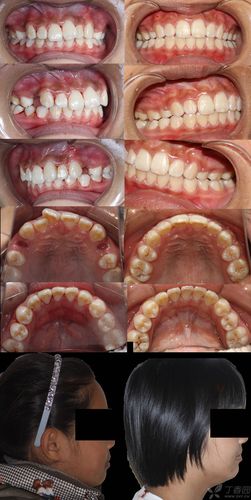

病例分析是直播的核心板块之一,曾教授会选取典型病例(如严重拥挤、开颌、深覆颌等)进行全流程复盘,包括患者初诊照片(口内口外)、X线头影测量数据分析、阶段性矫治效果对比及最终保持方案设计,针对治疗中的失败案例或并发症(如牙根吸收、复发问题),也会坦诚剖析原因,如何规避风险”“如何与患者有效沟通预期”等临床经验,强调正畸治疗不仅是“排齐牙齿”,更是“功能与美学的平衡”。

| 病例实战 | 典型病例全流程复盘(初诊-治疗-保持)、失败案例反思、医患沟通要点 | 病例影像展示、阶段效果对比 | 严重拥挤病例的拔牙与非拔牙方案选择;开颌病例的病因分析 |